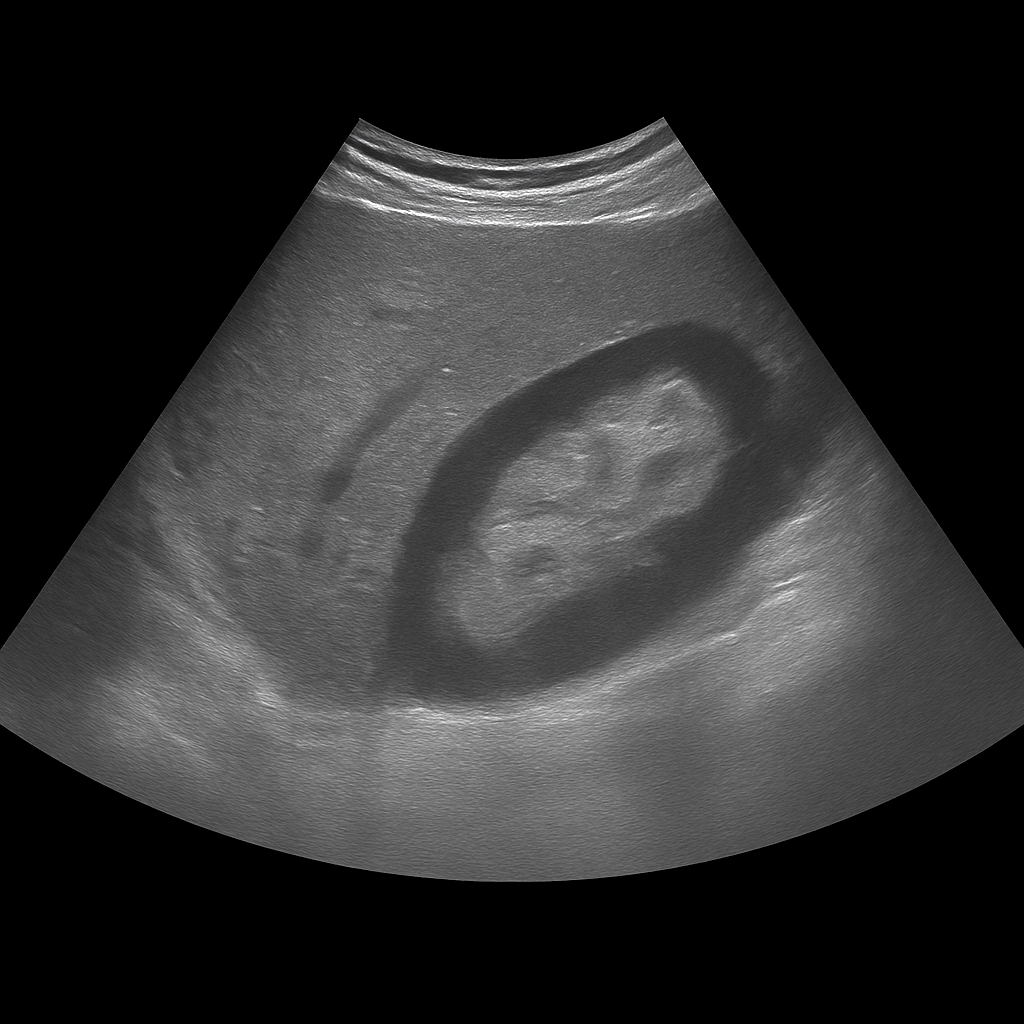

- Ultrasound of the abdomen shows the liver, gallbladder, pancreas, kidneys and other abdominal organs in real time.

- Recommended for abdominal pain, swelling, nausea or elevated liver values.

- Quick, painless and radiation-free examination of the internal organs of the abdomen.

- Written opinion and recommendation from a specialist doctor are included.